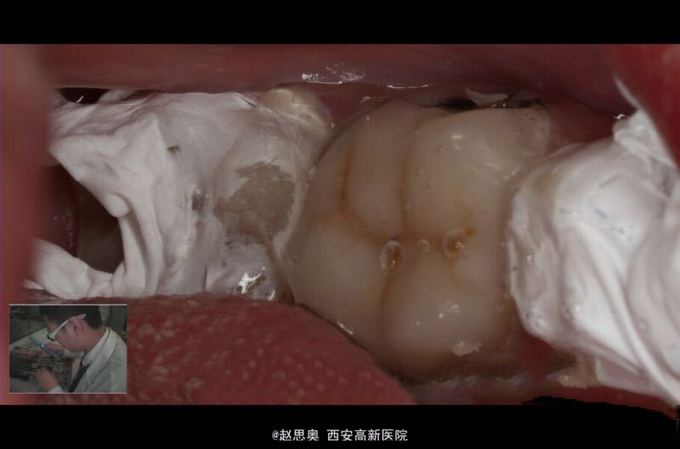

患者女,31岁,患牙龋坏致牙体缺损,自发疼痛求诊

诊断为不可复性牙髓炎,慢性根尖周炎 处理,根管治疗后间接树脂修复